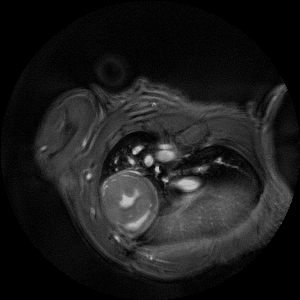

• Crisp and highly resolved images with native gradient strength of 740 mT/m, upgradable to 1000 mT/m

• MRI CryoProbe for exceptional increase in sensitivity

• MRI sequence portfolio of more than 1,000 sequence variations, including wireless cardiac imaging using navigator based IntraGate methods with cartesian or radial readout, as well as short echo time imaging, such as UTE and ZTE